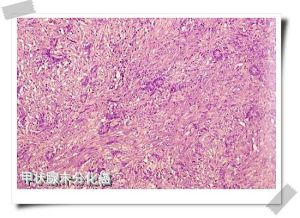

(1)肉眼觀:腫塊較大,病變不規則,無包膜,廣泛浸潤、破壞,切面灰白,常有出血、壞死。(2)鏡下:癌細胞大小、形態、染色深淺不一,核分裂像多。組織學上可分為小細胞型、梭形細胞型、巨細胞型和混合細胞型。可用抗Keratin、CEA及thyroglobulin等抗體作免疫組織化學染色證實是否來自甲狀腺腺上皮。

甲狀腺未分化癌(2)鏡下:癌細胞大小、形態、染色深淺不一,核分裂像多。組織學上可分為小細胞型、梭形細胞型、巨細胞型和混合細胞型。可用抗Keratin、CEA及thyroglobulin等抗體作免疫組織化學染色證實是否來自甲狀腺腺上皮。